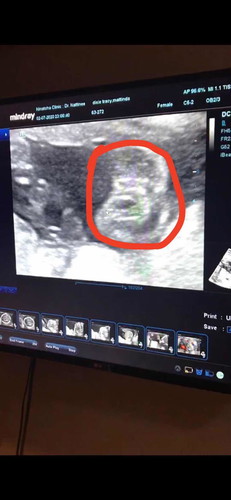

แบบนี้คือกลีบจิมิของลูกใช่มั้ยคะ 555 สรุปลูกสาวใช่มุ้ยย5555